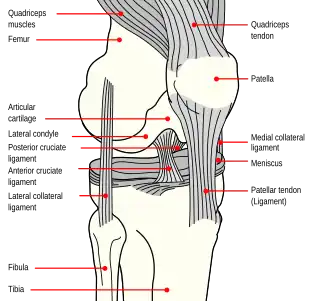

The patella (pl.: patellae or patellas), also known as the kneecap, is a flat, rounded triangular bone which articulates with the femur (thigh bone) and covers and protects the anterior articular surface of the knee joint. The patella is found in many tetrapods, such as mice, cats, birds, and dogs, but not in whales, or most reptiles.

The patella is a sesamoid bone roughly triangular in shape, with the apex of the patella facing downwards. The apex is the most inferior (lowest) part of the patella. It is pointed in shape, and gives attachment to the patellar ligament.

The front and back surfaces are joined by a thin margin and towards centre by a thicker margin.[1] The tendon of the quadriceps femoris muscle attaches to the base of the patella.,[1] with the vastus intermedius muscle attaching to the base itself, and the vastus lateralis and vastus medialis are attached to outer lateral and medial borders of patella respectively.

The upper third of the front of the patella is coarse, flattened, and rough, and serves for the attachment of the tendon of the quadriceps and often has exostoses. The middle third has numerous vascular canaliculi. The lower third culminates in the apex which serves as the origin of the patellar ligament.[1] The posterior surface is divided into two parts.[1]

The upper three-quarters of the patella articulates with the femur and is subdivided into a medial and a lateral facet by a vertical ledge which varies in shape.

The primary functional role of the patella is knee extension. The patella increases the leverage that the quadriceps tendon can exert on the femur by increasing the angle at which it acts.

The patella is attached to the tendon of the quadriceps femoris muscle, which contracts to extend/straighten the knee. The patella is stabilized by the insertion of the horizontal fibres of vastus medialis and by the prominence of the lateral femoral condyle, which discourages lateral dislocation during flexion. The retinacular fibres of the patella also stabilize it during exercise.